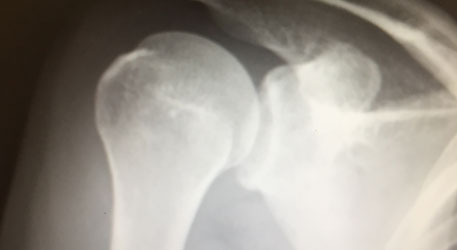

四十肩・五十肩は正式名称を「凍結肩(とうけつかた)」と言います。

そもそも「四十肩・五十肩」でない可能性がある

四十肩・五十肩の厄介なことの一つは

「これは四十肩・五十肩である」

と確定診断に繋がる検査や症状がないということです。

つまり診断の際には

- 肩が痛い

- 肩があがらない

このような症状が現れる他の疾患を全て否定しなければなりません。

ではこのような、四十肩・五十肩と似た症状が現れる疾患はどのようなものがあるのでしょうか?

- 腱板断裂

- 烏口上腕靭帯炎

- 上腕二頭筋長頭腱炎

- 石灰沈着性腱板炎

- 肩峰下滑液包炎etc…

はい。いっぱいあるんですね。